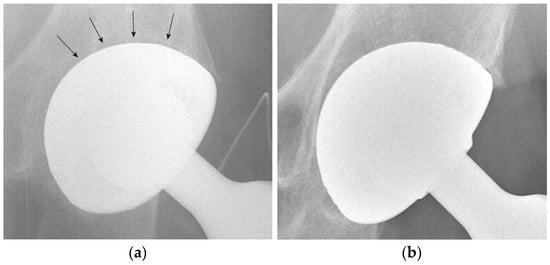

Radiographic signs of acetabular osteointegration at 1 year (Figure 2) were found in 42 patients (87.5%): 20 in the DMC group (83.3%) and 22 in the SC group (91.6%), with a non-significant difference (p-value = 0.98). No cases of implant mobilization were detected on X-rays. Heterotopic ossifications had a similar incidence in the two groups: four in the DMC group and three in the SC group (p-value = 0.99).

Figure 2.

(a) Postoperative radiograph of a DMC showing (arrows) a radiolucent line at the bone-implant interface. (b) Radiographic evidence of implant osteointegration one year after surgery.